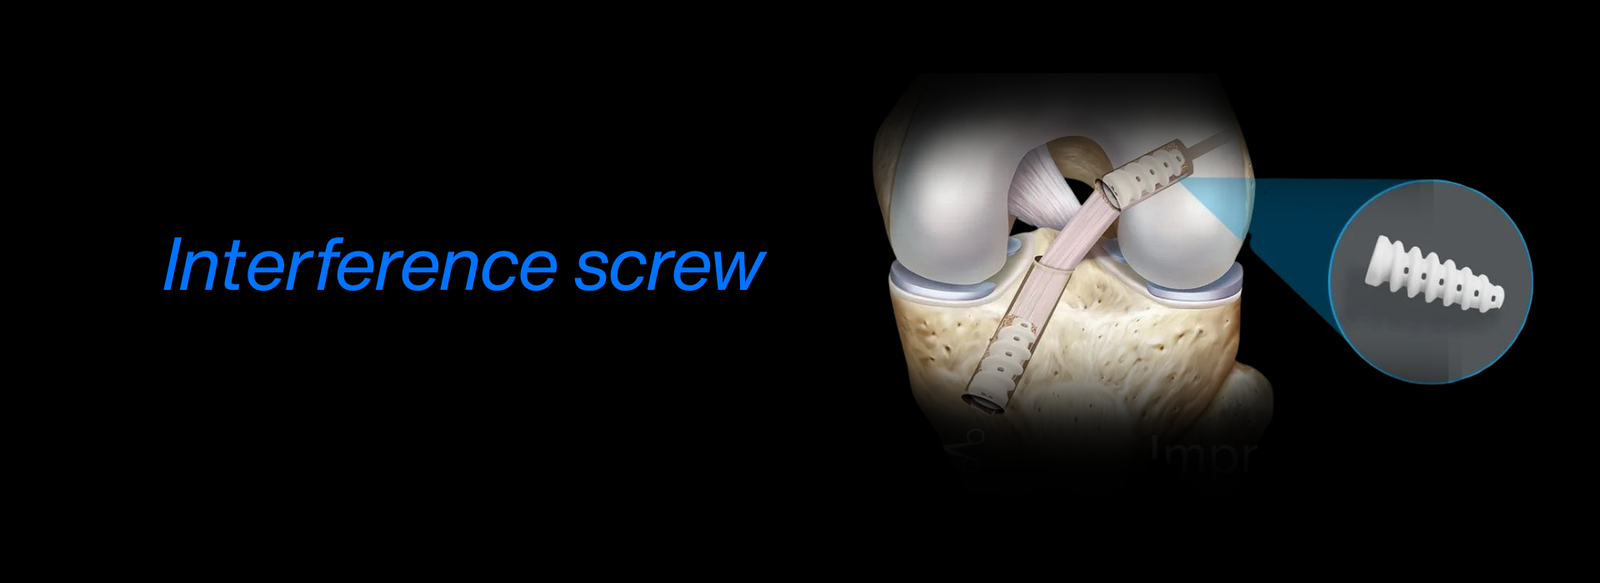

Fellowship in Arthroscopy: Expertise in minimally invasive surgery to diagnose and treat joint conditions, such as torn cartilage or ligament injuries, particularly of the knee, shoulder, and hip.